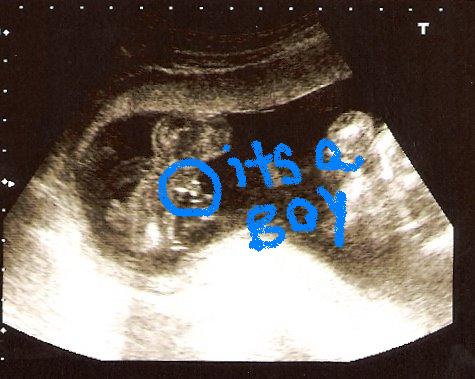

Re: Here are the sono pics from today

Congrats Julie!!!!

Wow, you really need a trained eye to tell, I can't tell.

I can't tell either! She said the 2 little dots were testicles and the bigger dot is the weenie